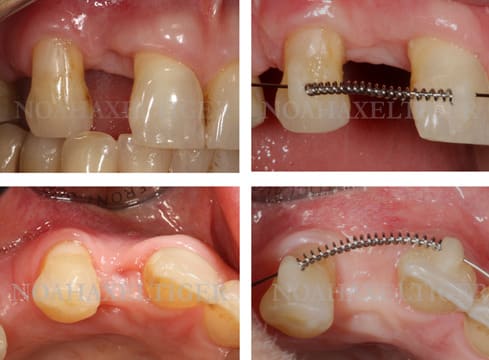

Suite du traitement, à quatre mois et sept mois.

A 7 mois, le fil NiTi ultrafin est toujours le même, il n’a pas été remplacé.

Observez l’absence de rotation parasite de 13 et la 12 qui s’est déplacée en vestibulaire !

Remarquez la simplicité du dispositif eu égard aux résultats obtenus.

En réalité, rien n’obligeait ici à déplacer tout de suite l’apex des dents hormis l’idéologie (commercialement très rentable….).

Reste à reculer un peu l’apex de 13 pour paralléliser sa racine avec les autres et permettre de vestibuler celle de 12. Cela pourra être fait avec des petits accessoires supplémentaires sur un fil un peu plus épais.

La suite en juin par manque de disponibilité de ma part avant.

Daniel